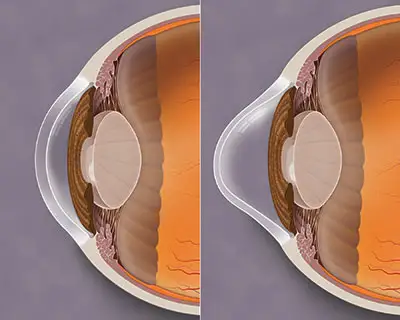

What are implantable collamer / contact lenses (ICLs)?

Implantable collamer lenes (also called implantable contact lenses) are soft lenses that may be placed inside the eye. This is a refractive procedure (like LASIK) which may take the place of glasses or soft contact lenses. ICLs take the place of strong glasses or soft contact lenses and may correct large amounts of near-sightedness and/ or astigmatism. Implanting these lenses is regarded as a minor procedure and is typically done in the office. Most insurance plans do not currently cover ICL implantation.